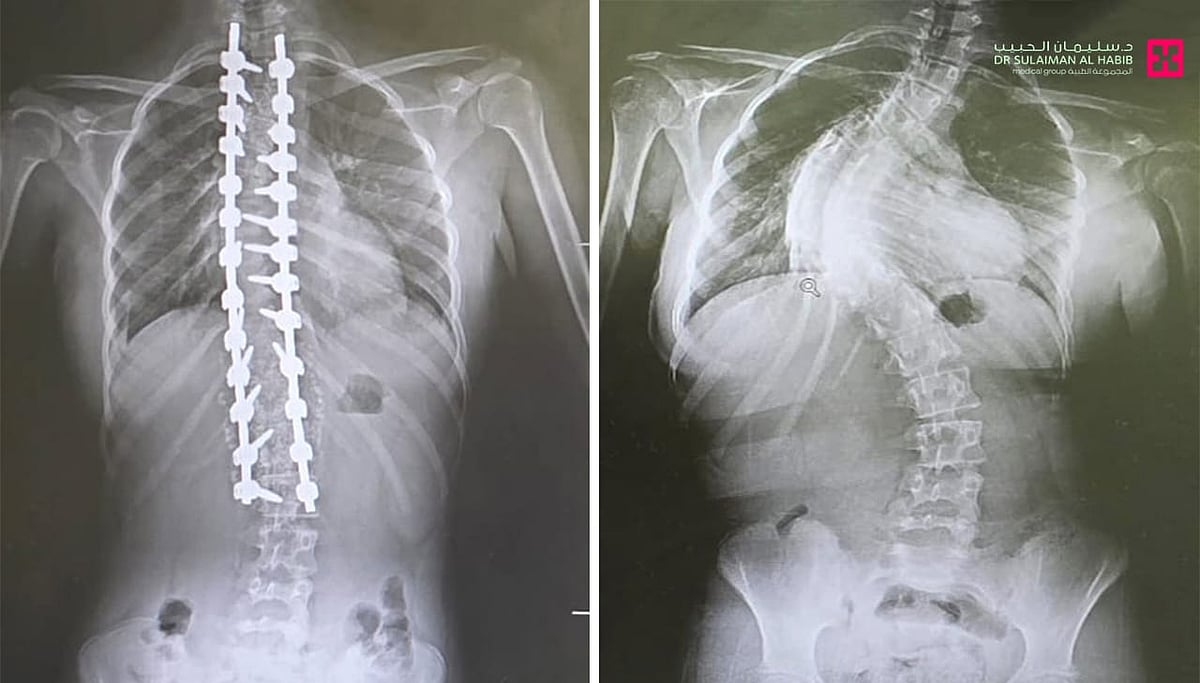

يشهد مستشفى الدكتور سليمان الحبيب بالقصيم نجاحات متتالية في مجال جراحة العمود الفقري، حيث أعلن المستشفى مؤخرًا عن إتمام عملية جراحية دقيقة ومعقدة لتصحيح انحراف العمود الفقري (الجنف) لطفلة كانت تعاني من آلام حادة ومشاكل صحية متعددة. هذه العملية، التي استمرت سبع ساعات متواصلة، تمثل بصيص أمل للكثيرين ممن يعانون من هذه الحالة، وتؤكد على كفاءة الكوادر الطبية المتخصصة في المستشفى.

تم إجراء العملية الجراحية المعقدة لطفلة كانت تعاني من انحراف متزايد في العمود الفقري، وهو ما يعرف علميًا بالجنف. هذا الانحراف كان يسبب لها آلامًا شديدة، وصعوبة في التنفس، بالإضافة إلى تأثيرات سلبية على وظائف القلب والأوعية الدموية. الفريق الطبي المعالج، بقيادة الدكتور ناجي مسعود، استشاري جراحة المخ والأعصاب والعمود الفقري، والدكتور صلاح الدين خليفة، استشاري جراحة العظام والعمود الفقري، قام بتقييم دقيق للحالة وتحديد أفضل خطة علاجية.

ركزت العملية الجراحية على تثبيت ودمج الفقرات المنحرفة، وذلك باستخدام أحدث التقنيات والمواد الطبية. يهدف هذا الإجراء إلى استعادة الشكل الطبيعي للعمود الفقري، وتخفيف الضغط على الأعصاب، وتحسين وظائف الجسم بشكل عام. تم استخدام نظام تثبيت متطور يضمن استقرار الفقرات المدمجة، ويسمح للمريضة باستعادة قدرتها على الحركة والنشاط بشكل تدريجي.